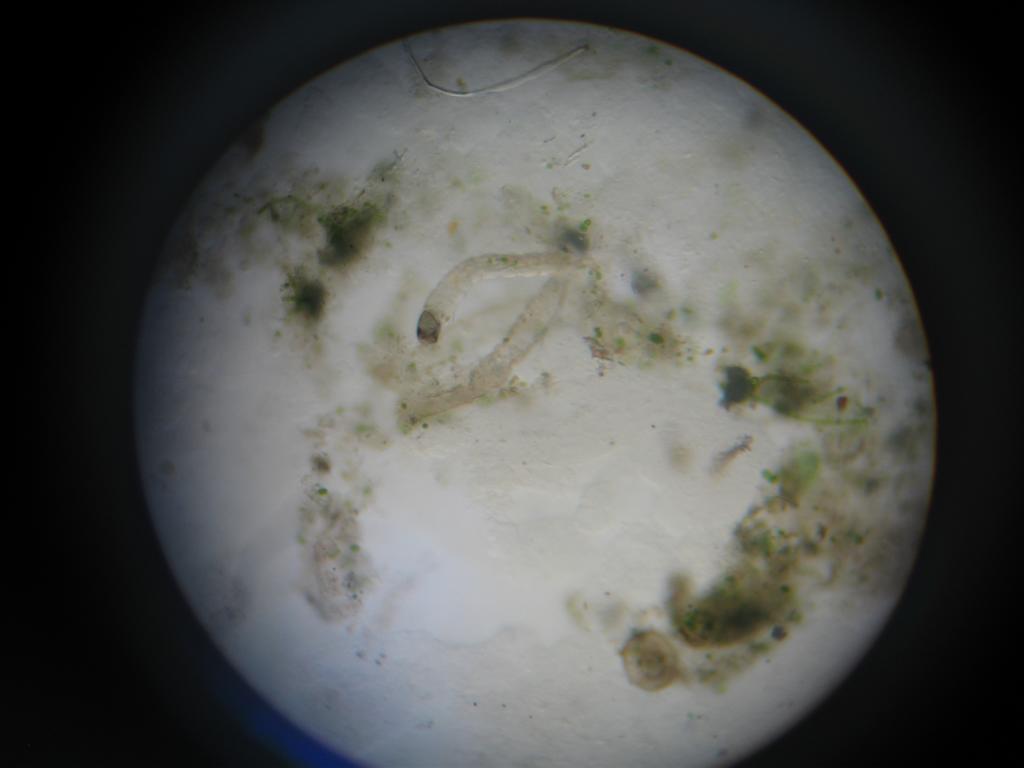

Die gefundenen Parasiten konnten wir trotz eines Buches nicht genau bestimmen aber es scheinen irgendwelche Würmer zu sein. Zusätzlich gab es da noch ein "Pünktchen", welches sehr schnell durch das Bild gewuselt ist.

Ich habe hier ein paar Bilder, vielleicht könnt Ihr daran etwas erkennen. Ich will nicht irgendein Medikament bestellen und damit experimentieren.

Auf den Bildern sind keine typischen Parasiten erkennbar,

das was da zu sehen ist , scheinen eher Tierchen ,

welche sich um abgestorbenes Material/Gewebe kümmern.

Felix hat geschrieben:

Zusätzlich gab es da noch ein "Pünktchen", welches sehr schnell durch das Bild gewuselt ist.

war das das wuselnde Pünktchen ?

Bild

Sieht so in etwa nicht Trichodina aus?